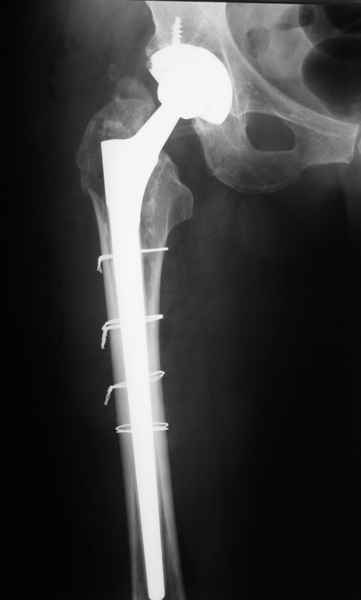

Уважаемые коллеги, продолжая дискуссию, начатую на "Вреденовских чтениях", хочу сказать, что принципиально сущестует два возможных варианта лечения.

1.Остеосинтез на ножке. Мне кажется, что применительно к этому случаю малоперспективный вариант. Синтез хорош, когда можно его выполнить в малоинвазивном исполнении и достигнуть стабильности. Действительно, если ножка б/цементной фиксации после этого не будет иметь фиксации, то ревизия не будет иметь проблем. В представленном случае стабильность синтеза сомнительная, а проведение доп.иммобилизации приведет к контрактуре суставов.

2. Применение ножки дистальной фиксации, мы отдаем предпочтение ножке Вагнера с фиксацией проксимального отдела на ножке. Более травматичное вмешательство, но при стабильной фиксации ножки реабилитация идет в обычном режиме.

Хочется показать два подобных случая, П-ка З. 72 лет и п-т Г. 80 лет. Сразу принимаю замечание, что это были ножки цементной фиксации, просто под руками не было бесцементника.

С уважением, Р.Тихилов